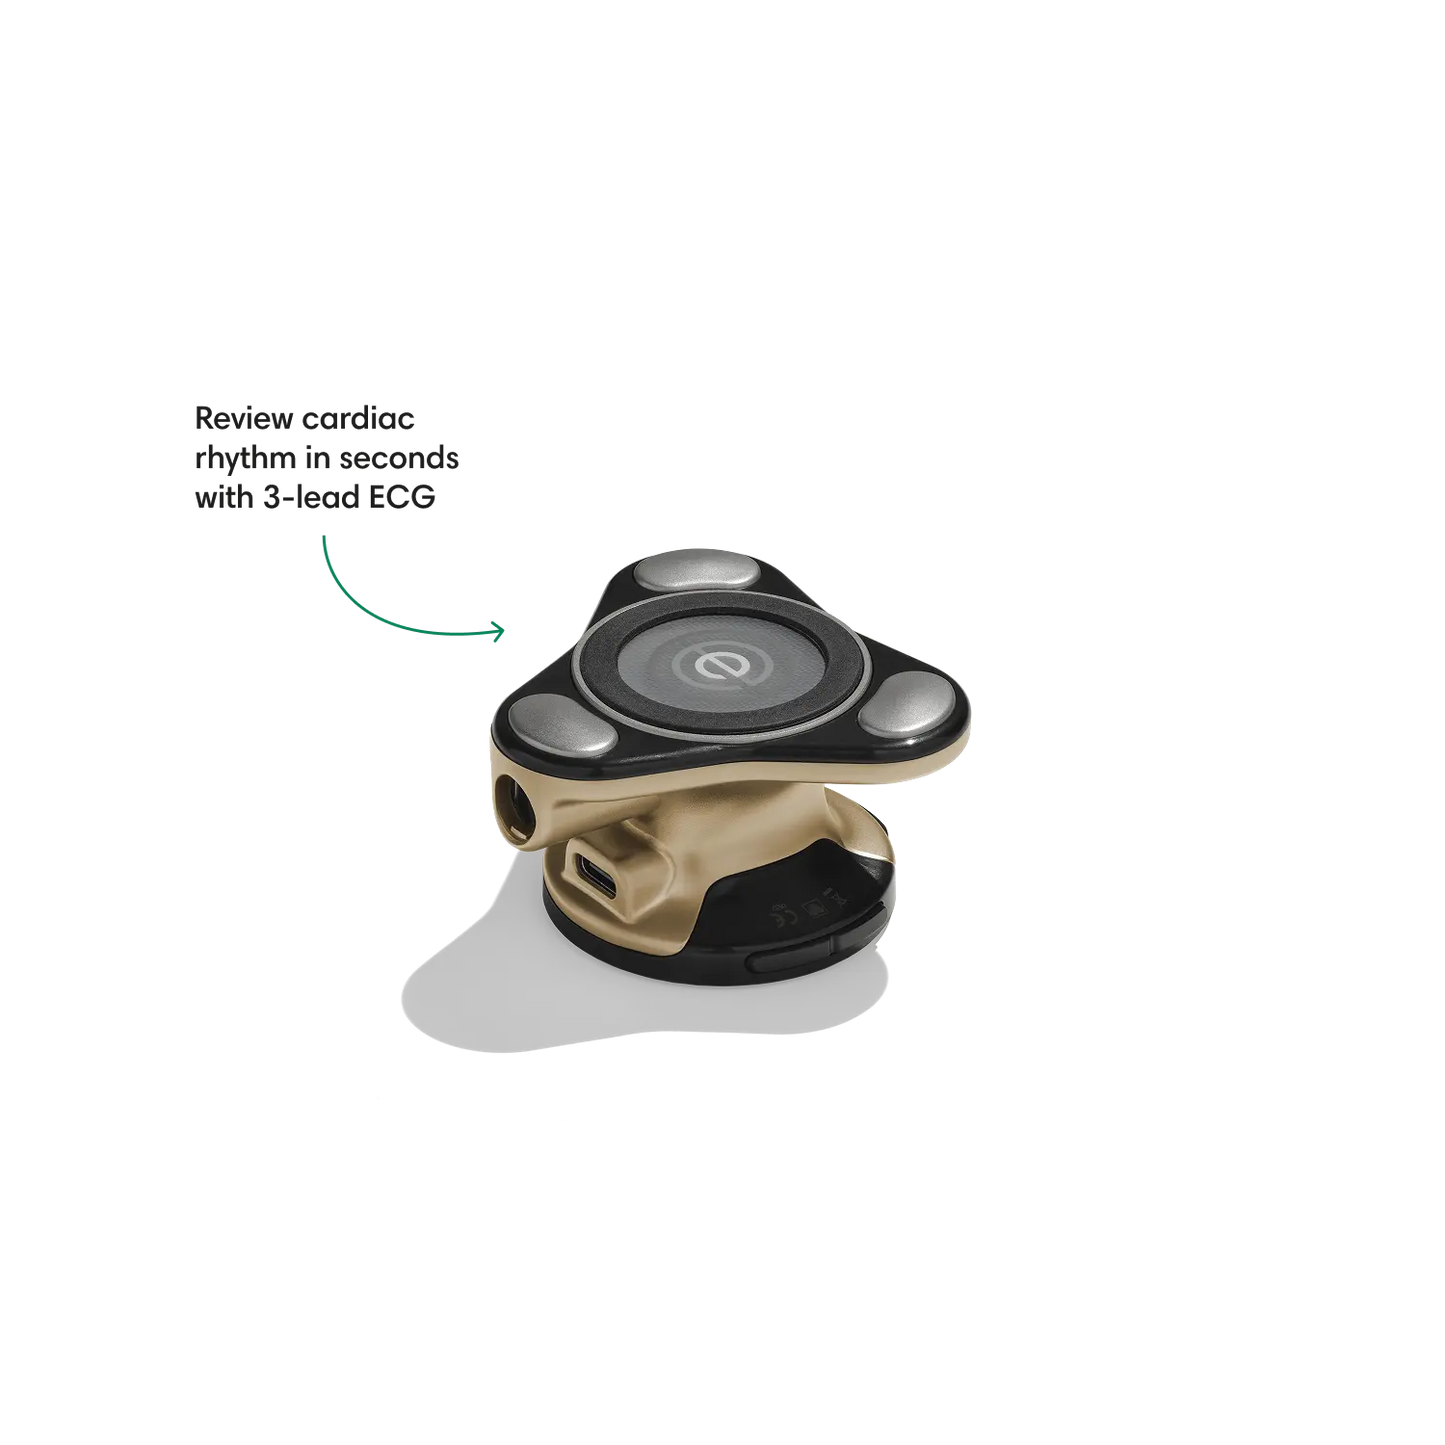

Go beyond sound alone.

For the first time ever, measure heart rate, visualize 3-lead ECG, and see detection results — right on a built-in, full-color display.